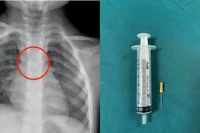

Ngày 21/1, Bệnh viện hữu nghị Việt Nam–Cuba Đồng Hới, tỉnh Quảng Trị cho biết, vừa phẫu thuật cấp cứu thành công 1 trường hợp thanh niên bị đinh từ súng bắn đinh xuyên thành bụng, thủng ruột non trong lúc lao động.

Trước đó, bệnh nhân N.Đ.T. (sinh năm 1993), trú tại xã Ninh Châu, tỉnh Quảng Trị được đưa vào bệnh viện trong tình trạng đau bụng nhiều sau khi bị súng bắn đinh bắn trúng vùng bụng khi đang làm việc. Ngay khi tiếp nhận, các bác sĩ tiến hành thăm khám lâm sàng và chụp cắt lớp vi tính ổ bụng.

Kết quả cho thấy dị vật là một chiếc đinh đã xuyên qua thành bụng trái và găm trực tiếp vào ruột non, tiềm ẩn nguy cơ nhiễm trùng ổ bụng và biến chứng nặng nếu không xử trí kịp thời.

Trước tình trạng nguy cấp, các bác sĩ Khoa Ngoại Tổng hợp đã nhanh chóng chỉ định phẫu thuật nội soi cấp cứu. Ê-kíp tiến hành lấy dị vật, khâu lỗ thủng ruột non, đồng thời khâu phục hồi thành bụng. Sau mổ, bệnh nhân tỉnh táo, các chỉ số sinh tồn ổn định và đang được theo dõi hậu phẫu.

Bác sĩ Phan Lê Khanh, người trực tiếp phẫu thuật, cho biết đây là trường hợp may mắn vì bệnh nhân được đưa đến bệnh viện sớm. Nhờ đó, ổ bụng còn khá sạch, không ghi nhận thức ăn hay dịch tiêu hóa tràn ra ngoài. Trong quá trình thám sát, ê-kíp không phát hiện tổn thương đại tràng hay các mạch máu lớn, giúp ca phẫu thuật diễn ra thuận lợi.